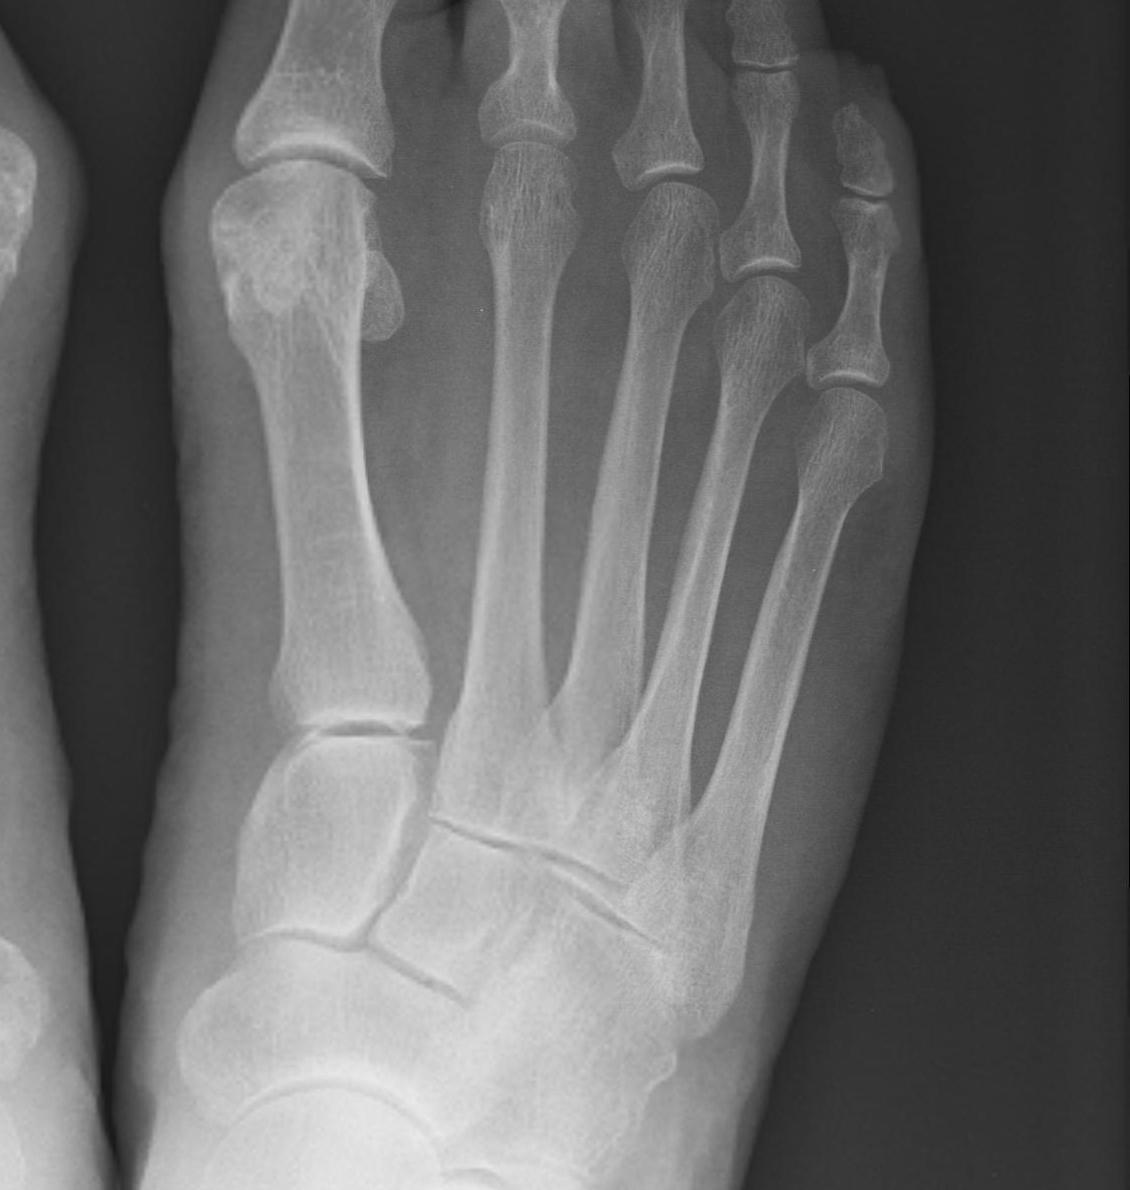

1. Diastasis of the intermetatarsal gap between the 1st and 2nd metatarsals

2. Widening of the space between the medial cuneiform and base of 2nd metatarsal

3. Second metatarsal Fleck sign - avulsion of Lisfranc ligament from base of 2nd metatarsal

4. Widening of inter-cuneiform distance

6. Tarsometatarsal alignment disruption

- medial border 1st metatarsal aligns with medial border medial cuneirform (AP foot)

- medial border 2nd metatarsal aligns with medial border middle cuneiform (AP foot)

- medial border 3rd metatarsal aligns with medial border lateral cuneiform (AP view)

Subtle widening of the medial cuneiform - 2nd metarsal distance, and the inter-metatarsal distance